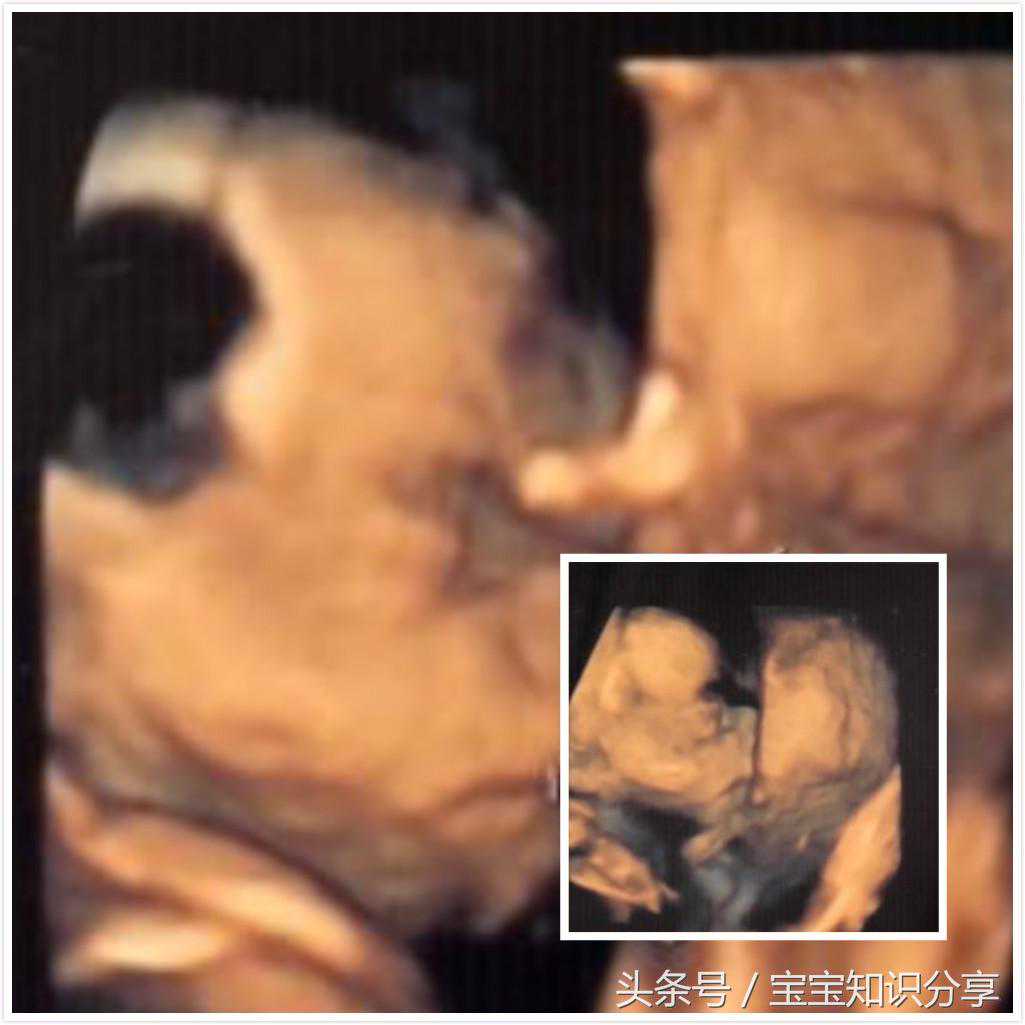

第三次产检:孕23W三维大排畸

检查那天下着雨,气温又低,没想到我们却因祸得福。省妇幼竟然空荡荡的没几个人影。而我的宝宝果然跟我期望中一样配合,拿到报告时,才9:38.后来渐渐发现我们彻底被省妇幼逼成了神经病,专挑大风大雨的日子去产检,就为了少排下队。

我感觉我从躺下去到站起来,也就十多分钟时间,其间医生一言不发。到我起来时,有个妹子进来了,果然,是第一次失败走了一圈儿又回来的。而我,顺利地一次通过!

拿到报告时,看了一眼照片,当时脑子里蹦出来的第一句话是:

退不了货了!亲!(一个孕妈APP里的话)

我做梦也没有想到我的宝宝会不漂亮。我担心TA的一切,除了长相。可是,我好像突然遭遇了一个致命打击!

当然这只是一瞬间的事,接着我看报告上的文字,看到呼吸一项,写着未见,立马头顶一个焦雷。赶紧跑去找到老公,老公一看还有“建议复查”的字样,也慌了,我们赶紧下楼去问门诊医生。结果只是一场虚惊,呼吸出生之后才会有。

还有一件神奇的事,这一次的报告显示我的胎盘长后壁去了。我又百度,这是不可能的情况,所以,我想肯定是某一个医生弄错了。反正也无伤大雅,随它去吧!

只是,我后来好几天,还时不时会拿出照片来看,宝宝到底像谁呢?